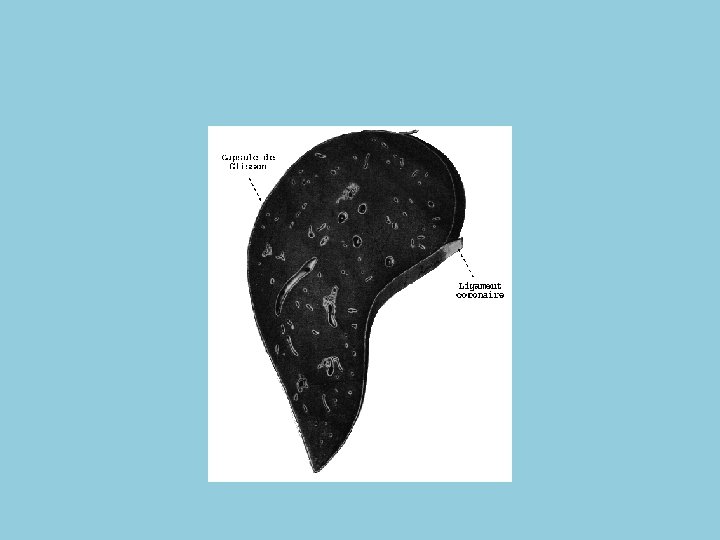

Configuration extérieure et rapport • Dans son ensemble, le foie peut être comparé au segment supérieur d'un ovoïde dont le grand axe serait transversal, la grosse extrémité à droite et qu'on aurait sectionné de gauche à droite, suivant un plan incliné regardant en haut, en avant et à droite. La surface du foie est lisse. Il présente 2 faces et deux bords.

Anatomie 2 • La face diaphragmatique est convexe, lisse, unie. Elle comporte 3 segments : le segment antérieur, le segment supérieur et le segment postérieur. • le segment antérieur entre en contact avec la paroi abdominale antérieure. Il est parcouru par l'insertion du ligament falciforme (ligament suspenseur) qui le divise en 2 bords (droit et gauche). • le segment supérieur se moule en haut sur la concavité du diaphragme. Sa partie latérale droite est à peu près entièrement recouverte par la cage thoracique et s'élève, comme le diaphragme, jusqu'au quatrième espace intercostal. • le segment postérieur est vertical et présente une concavité transversale très prononcée, qui s'adapte à la saillie de la colonne vertébrale. Il est limité en bas par le bord postérieur.